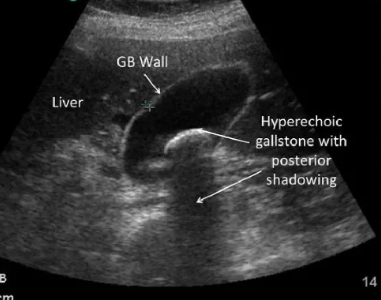

¿Para qué sirve USG?

*Permite ver presencial de litos (sombras posteriores)

* Ancho de vesícula (3-6 mm hasta 9mm) 10 mm es dilatado

* Grosor de pared (3-4mm)

* Nos dice como está páncreas, colédoco, , hígado, más vía extrahepática

¿Cuándo se considera colescistitis aguda?

Pared engrosada en USG de más 4mm